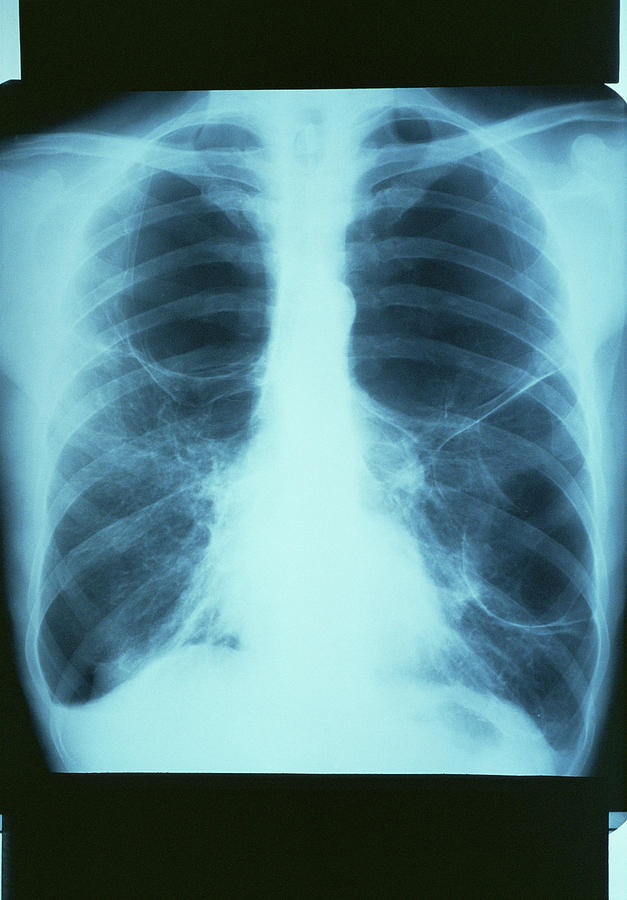

Рентгеновские снимки при врожденной эмфиземе легкого

Раздел: Визуальные уроки